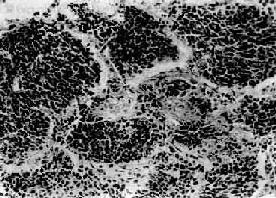

(2)小细胞癌:发生率在肺癌中居第二位(临床统计在40%以上,尸检统计占15%~25%)。患者男多于女(20:1),发病年龄约在35~60岁。小细胞肺癌亦多发生于肺中央部,生长迅速,转移较早,恶生度高,5年存活率仅1%~2%。小细胞癌的癌细胞很小,呈短梭形或淋巴细胞样,有些细胞呈梭形或多角型,胞浆甚少,形似裸核。癌细胞常密集成群,由结缔组织加工分隔(图9-33)。有时癌细胞围绕小血管排列成假菊形团或管状结构。小细胞肺癌起源于支气管粘膜和粘液腺内Kultschitzky细胞,是一种具有异源性内分泌功能的肿瘤。

图9-33 小细胞肺癌

短梭形癌细胞平行排列,群集成团(燕麦细胞型)